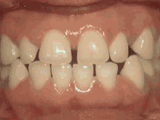

spacing of teeth

Patient was bothered by the spaces between his teeth. Braces closed the spaces and gave him an ideal bite in twenty-four months. Special glued-in retainers help keep the spaces closed.